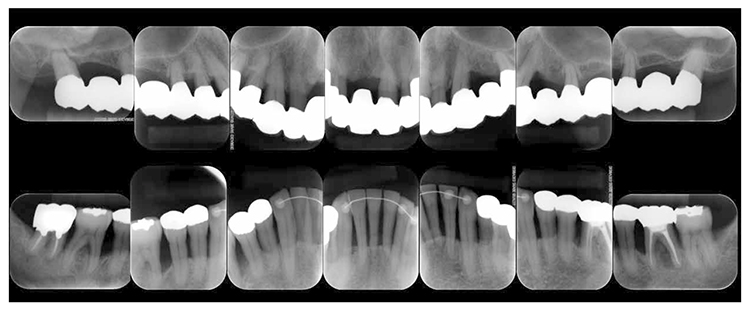

After transitioning to SPT, the patient brushed 4 times daily after every meal and before bedtime and has continued to use an interdental brush. PCR levels have been consistently in the 20% range. SPT , which primarily consists of instructions on brushing and dental surface cleaning, has been implemented every other month to present, and efforts are made to maintain and manage oral hygiene in the long term to ensure that plaque control is not insufficient. While minor discoloring is observed on the prosthetics, the color of the gingiva is salmon pink and a macroscopically healthy appearance has been sustained (Fig.7a) . The average PD on the entire jaw is 2.1mm,maximum PD is 4.0mm,the ratio of PD of 3mm or less is 99.3%. No BOP has been found and the condition of the periodontal tissue has been stable (Fig.7b). In the X-ray, continuity of the alveolar hard line has been replicated and the sequence of the bone trabeculae has been normal (Fig.7c).

Fig 7c

(Fig.7c) 15 years after first visit: dental X-ray 14 (December 2022)